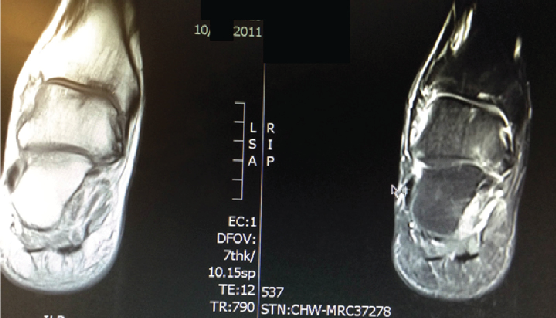

The patient’s physical exam was significant for tenderness to palpation across the ankle joint with pain on active and passive range of motion. He was neurovascularly intact. The patient had clinical and radiographic evidence of a 1.4 cm osteochondritis dissecans as shown in an MRI from March 2011.

After injections only alleviated his pain for one day, we decided to perform arthroscopically assisted retrograde drilling in July 2011. The patient wore a weightbearing controlled ankle motion (CAM) walker with limited time in dependency for four weeks followed by four weeks of physical therapy. He subsequently described his pain level as level 2 at the end of September. By October, the patient was functioning normally as he was walking without pain and any bracing.